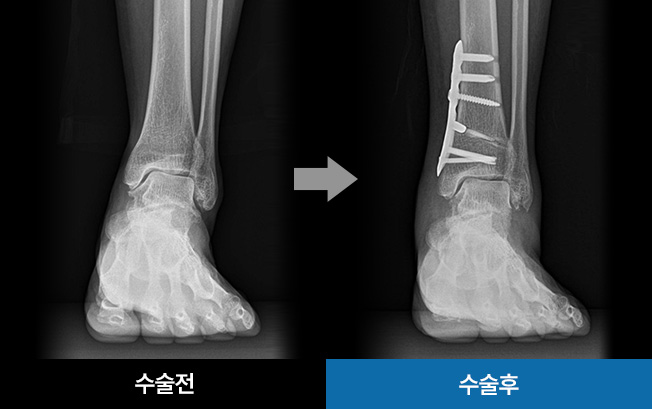

발목관절염은 발목 뼈를 보호하는 연골이 점차 닳아서 통증과 부종을 유발하는 질환입니다. 약물치료,

주사치료, 물리치료 등 발목관절염 초기에는 보존적 치료가 가능하지만 심한경우 관절내시경, 발목고정술,

인공관절 수술이 필요할 수 있습니다.

발목교정술